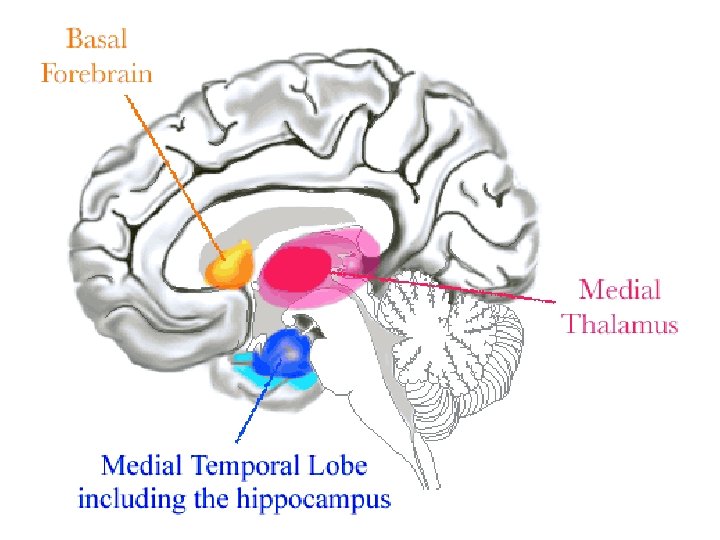

Bauer, Grande, & Valenstein, 2003

Integrated Circuitry Linking Temporal, Diencephalic, and Basal Forebrain Regions

Basal Forebrain Anatomy